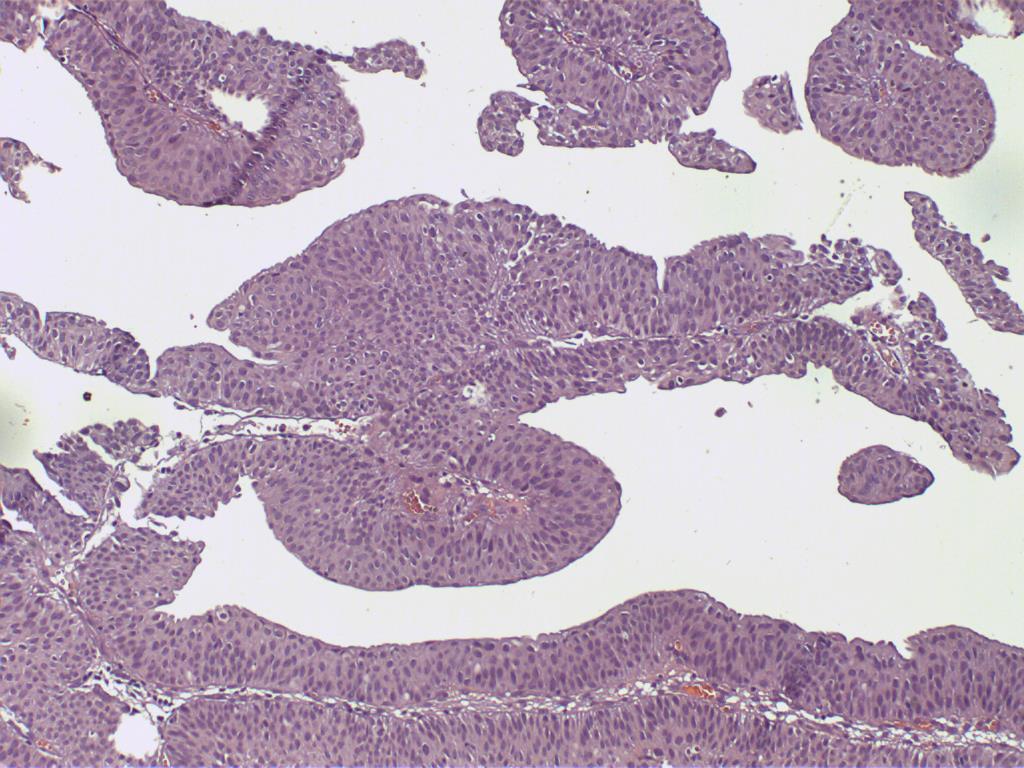

Bladder Papillary Lesions

Case ID: 487